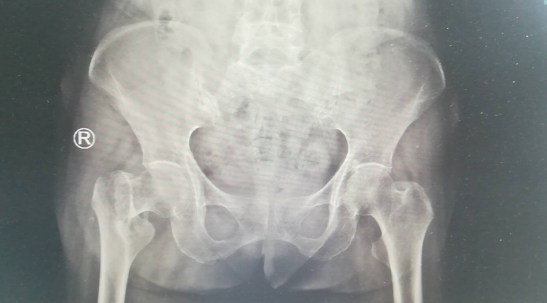

摔倒后吴老太的活动明显受限,无法站立,家人见状就把老人送到当地医院拍片,结果是右股骨粗隆间骨折,赶紧又把老人送到betway在线登陆,关节科郝亮医生接待了这位老人。

检查显示,老人不但是右股骨粗隆间骨折,询问后还有高血压病、脑梗死、房性早搏病史。